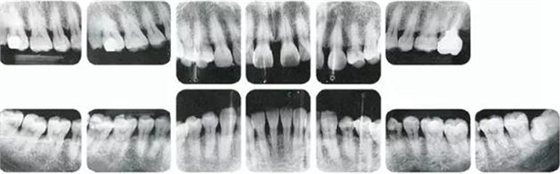

25歲女性。菌斑控制狀態(tài)不好。齦溝除磨牙處外全在3mm以下,X光照片上左上、右下、左下的第一磨牙上有垂直性骨吸收。這個(gè)病例是參考病例①10年前的狀態(tài),是典型的侵襲性牙周炎局部型。

牙周病的發(fā)展因部位不同而發(fā)展程度不同的。10點(diǎn)后的狀態(tài)參考病例①和參考病例②的磨牙處的狀態(tài)相比較,思考下沒接受治療病情發(fā)展的特別性吧。

參考病例① 35歲女性

在左下第一磨牙在25歲時(shí)近中處可以看到垂直性的骨吸收,但35歲時(shí)吸收停止,原本沒有見到的遠(yuǎn)中處骨吸收的,現(xiàn)在卻吸收得很嚴(yán)重。

在右下處,原本有大量骨吸收的第一磨牙處的吸收卻變緩慢,原本沒有吸收的第二前磨牙卻出現(xiàn)了吸收。出現(xiàn)吸收的左上第一磨牙的遠(yuǎn)中處,吸收得越來越多了。

把10年間的變化做成表格。牙周病的發(fā)展根據(jù)各個(gè)人會(huì)不同,即使通一個(gè)人,不同牙齒,不同牙面發(fā)展的狀態(tài)也不同。